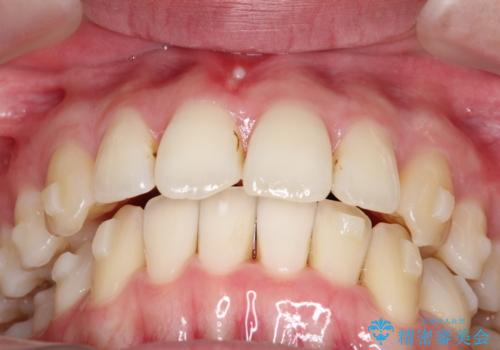

【インビザライン】 前歯の反対咬合を治したい

左下5番は先天性欠損のため乳歯は抜歯しインプラントにて欠損補綴しています。